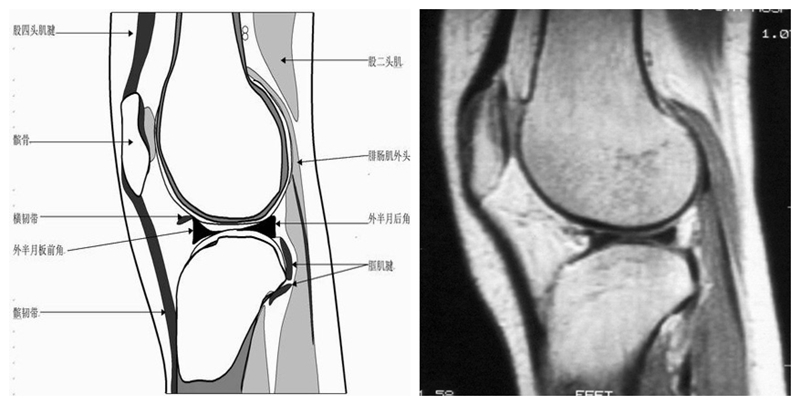

矢状位解剖第一层

矢状位解剖第二层